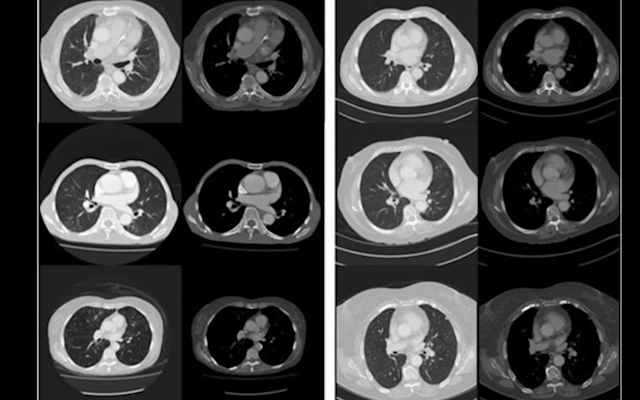

Se han presentado experimentos de prueba para demostrar cómo por la adquisición sistemática de imágenes a través de la TC de corte transversal se puede utilizar para predecir la longevidad del paciente como una guía para la salud individual y el estado general de la enfermedad mediante técnicas de análisis de imagen por ordenador. A pesar de las limitaciones de un conjunto de datos modesto y el uso de métodos de aprendizaje de la máquina, nuestros resultados son comparables a los métodos clínicos manuales previos para la predicción de la longevidad.

Investigadores de la Escuela de Salud Pública de la Universidad y la Escuela de Ciencias de la Computación, junto con colaboradores australianos e internacionales, utilizaron la inteligencia artificial para analizar la imagen médica de 48 pechos de pacientes. Este análisis computarizado fue capaz de predecir qué pacientes morirían dentro de cinco años, con el 69% de precisión, comparable a las predicciones «manuales» por los clínicos.

Presentamos un estudio preliminar de «prueba de principio» para evaluar la utilidad de la imagen médica para el fenotipado de la salud. Investigamos el análisis de la TC torácica de forma rutinaria en pacientes adultos (edad> 60) para predecir la longevidad. Elegimos la longevidad como nuestro resultado primario, ya que la mortalidad representa un resultado fácilmente obtenido y bien definido (en este caso, la tasa de mortalidad a los 5 años) y se correlaciona fuertemente con la presencia subyacente de enfermedad crónica. La fuerte relación entre la edad, la morbilidad y la mortalidad motiva la selección de la mortalidad a corto plazo como biomarcador sustituto para el estado general de salud. Las tomografías computarizadas son también la modalidad de imagen transversal menos variable a la estandarización de valores de píxeles y la relación definida entre los valores de píxeles y la densidad física del tejido. Finalmente, el tórax contiene tejidos directamente implicados en gran parte de la morbilidad y mortalidad en adultos mayores (es decir, en los pulmones, corazón, grandes vasos y otros órganos). Muchos de los métodos existentes de biomarcadores de imágenes cuantitativas relacionadas con la enfermedad crónica y la mortalidad utilizan CT imágenes de tórax.

Investigamos tanto el análisis de imagen tradicional con características definidas por humanos y técnicas de aprendizaje profundo («redes neuronales convolucionales») para esta tarea, ya que estas técnicas tienen diferentes fortalezas y debilidades. En particular, los métodos tradicionales de análisis de imágenes han sido previamente validados como un método para describir cambios sutiles en los tejidos, y el aprendizaje profundo ofrece el aprendizaje automático y sin hipótesis de características de imágenes complejas y de alto nivel.